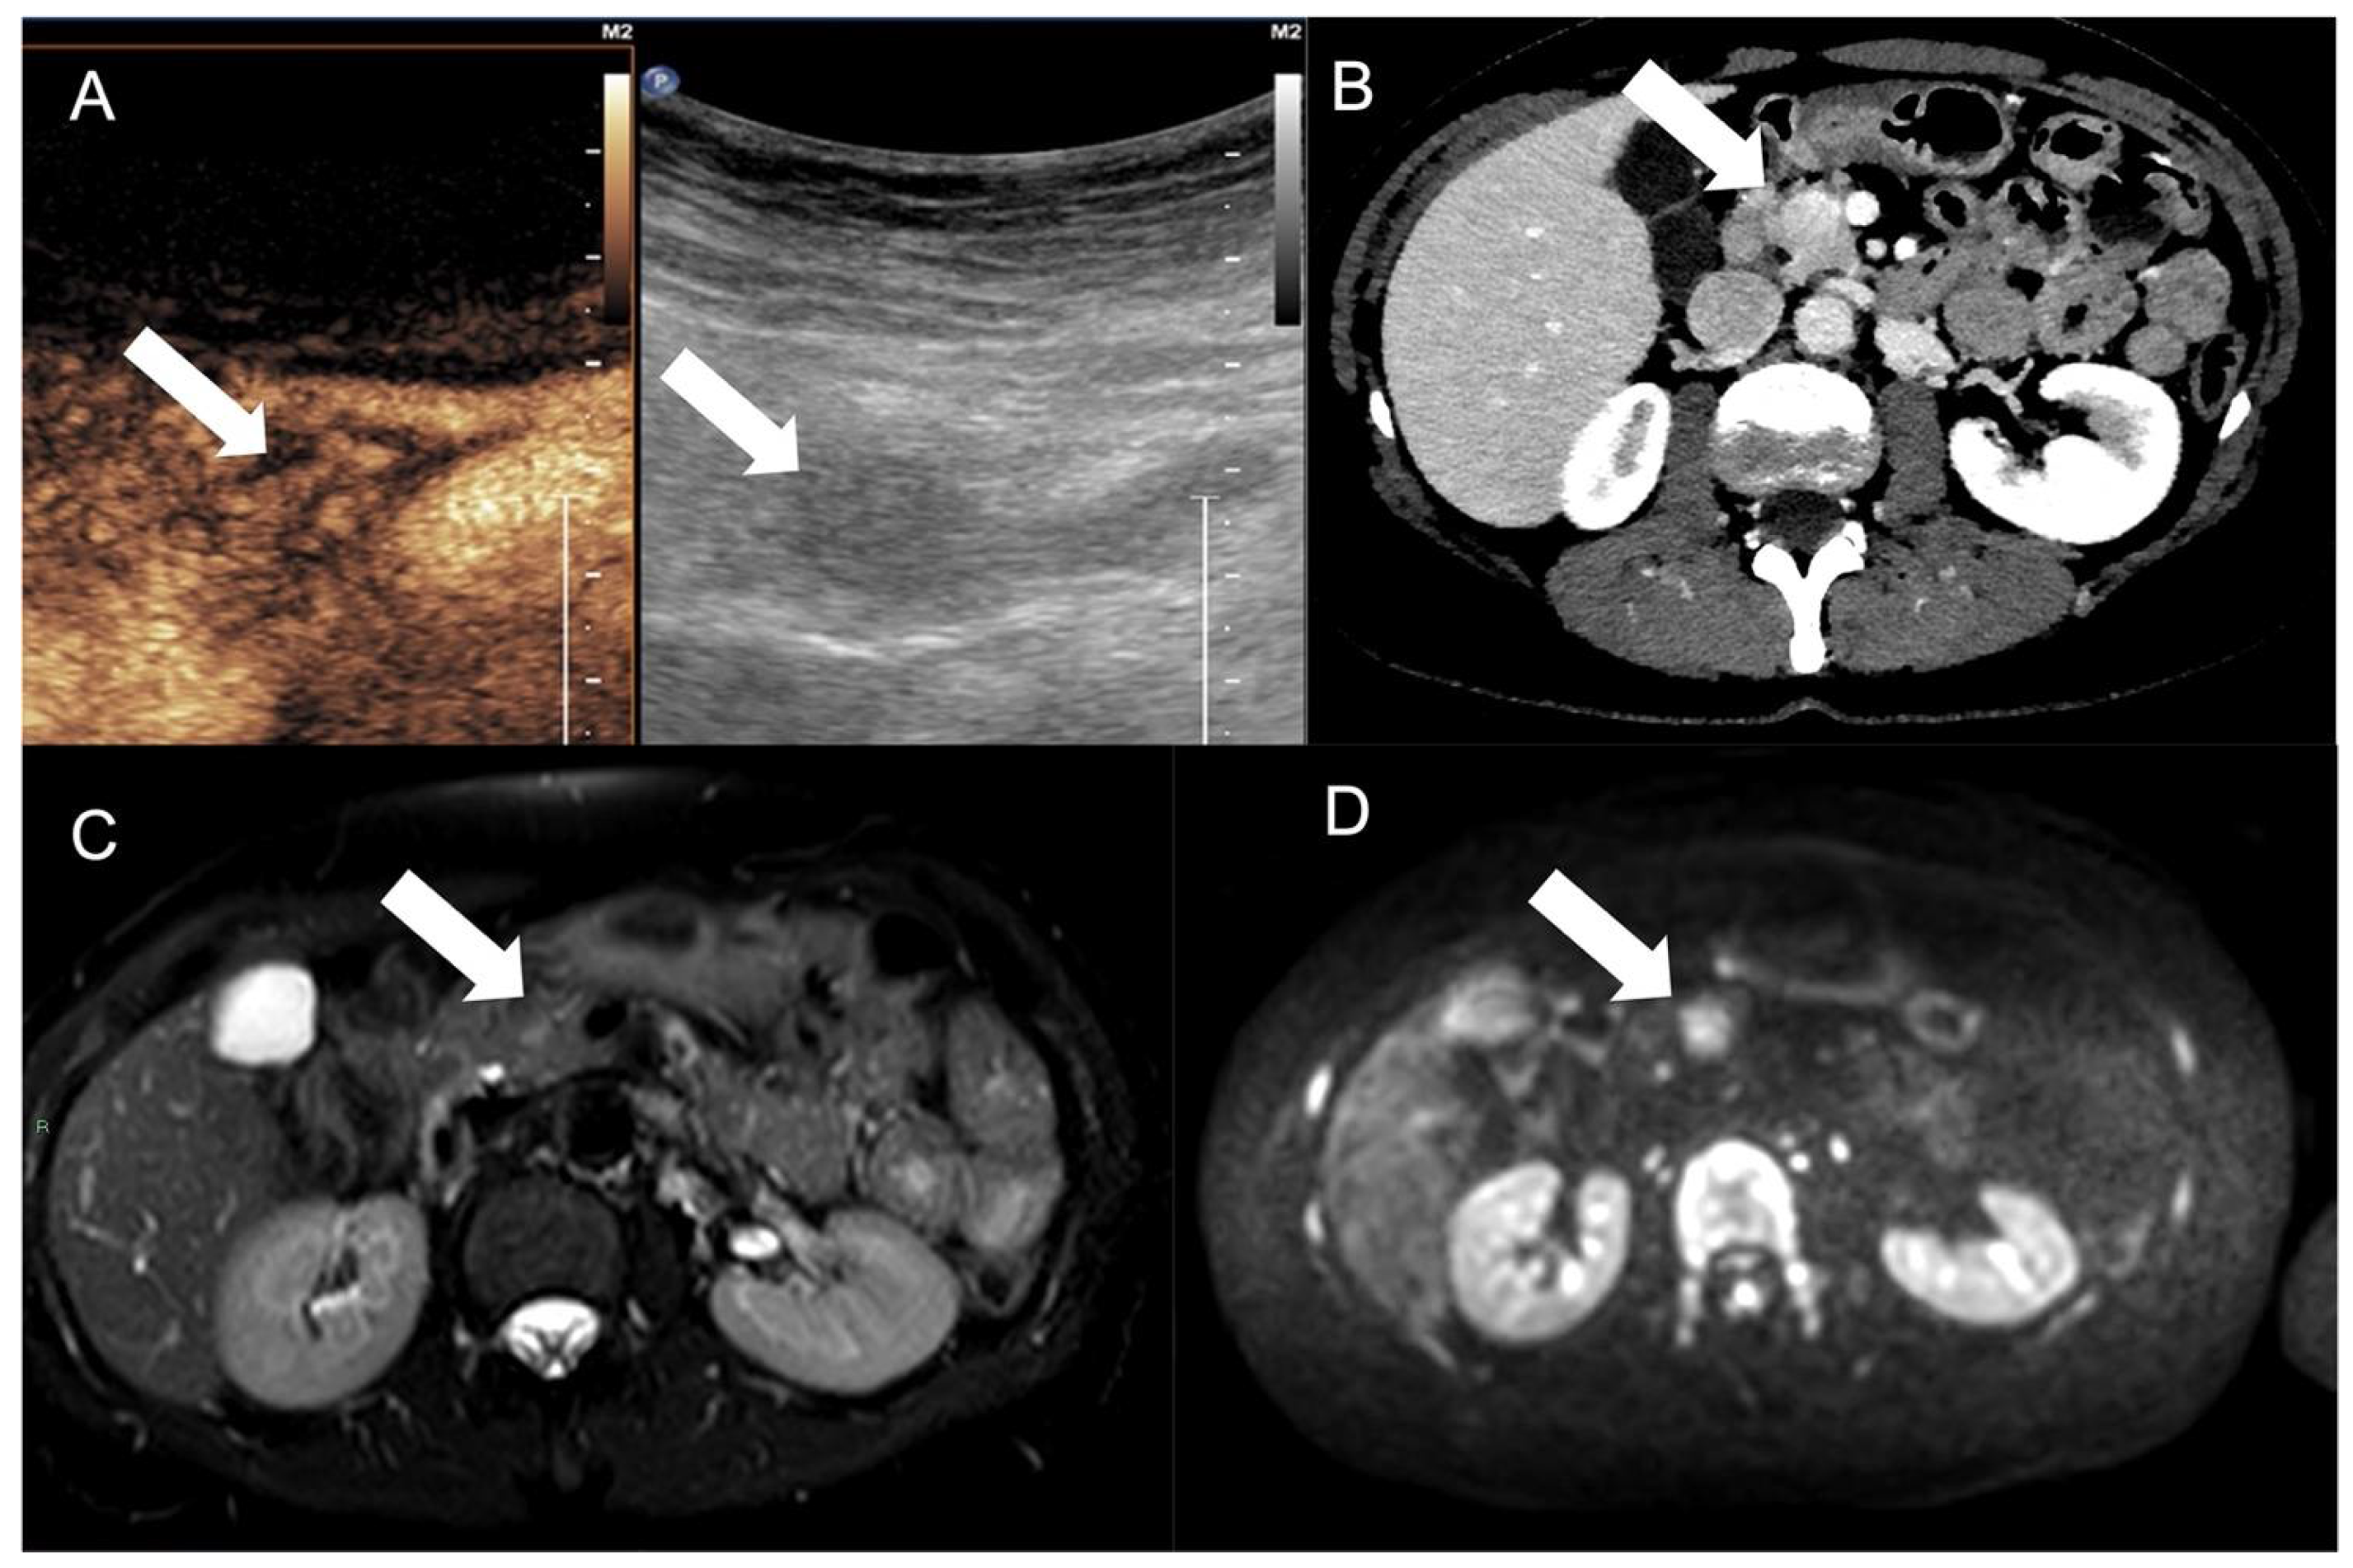

- G. d’Assignies; Fina, P.; Bruno, O.; Vullierme, M.; Tubach, F.; Paradis, V.; Sauvanet, A.; Ruszniewski, P.; Vilgrain, V. High sensitivity of diffusion-weighted MR imaging for the detection of liver metastases from neuroendocrine tumors: Comparison with T2-weighted and dynamic gadolinium-enhanced MR imaging. Radiology 2013, 268, 390–399. [Google Scholar] [CrossRef]

- Ronot, M.; Clift, A.; Baum, R.; Singh, A.; Kulkarni, H.; Frilling, A.; Vilgrain, V. Morphological and Functional Imaging for Detecting and Assessing the Resectability of Neuroendocrine Liver Metastases. Neuroendocrinology 2018, 106, 74–88. [Google Scholar] [CrossRef]

- Dromain, C.; de Baere, T.; Lumbroso, J.; Caillet, H.; Laplanche, A.; Boige, V.; Ducreux, M.; Duvillard, P.; Elias, D.; Schlumberger, M.; et al. Detection of liver metastases from endocrine tumors: A prospective comparison of somatostatin receptor scintigraphy, computed tomography, and magnetic resonance imaging. J. Clin. Oncol. 2005, 23, 70–78. [Google Scholar] [CrossRef] [PubMed]